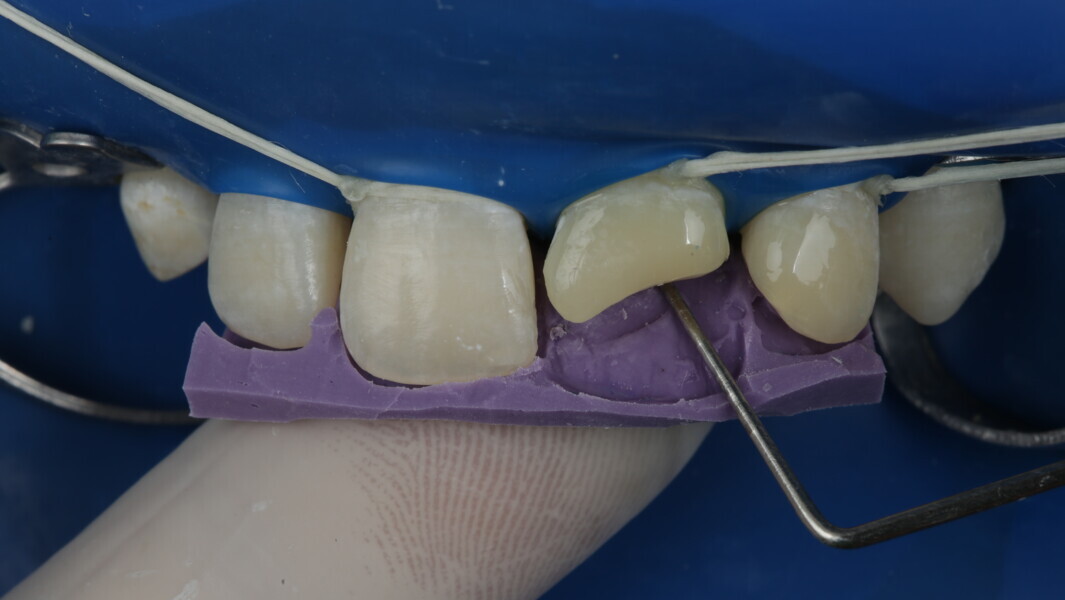

A 10-year-old male patient reported with a complaint of trauma to the upper left central and lateral incisors, involving the enamel and dentin. Direct composite was used in multi-layers and the smile was restored. This article explains detailed steps in the polychromatic layering technique with special emphasis on the finishing and polishing protocol. 3M Espe Filtex Z350 Xt was used with a universal bonding agent.

Fig 8-18: Bonding and palatal shell